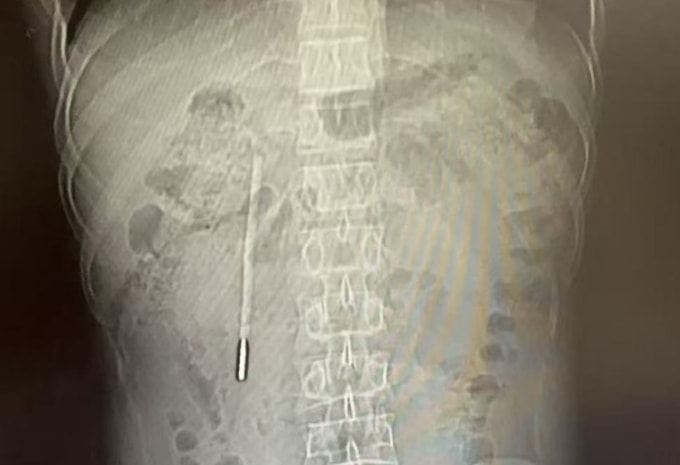

Truyền thông Trung Quốc đưa tin Wang đi khám do có triệu chứng đầy bụng, khó tiêu kéo dài. Kết quả chụp CT ổ bụng phát hiện một dị vật nằm ở tá tràng, được xác định là một chiếc nhiệt kế thủy ngân. Đầu nhọn của nhiệt kế đã tì sát vào thành ruột, có thể gây thủng ruột hoặc xuất huyết ồ ạt bất cứ lúc nào.

Đội ngũ y tế tại Trung tâm Nội soi của bệnh viện lập tức tiến hành thủ thuật lấy dị vật. Do chiếc nhiệt kế đã nằm trong cơ thể quá lâu, vị trí lại ở sâu và gần các bộ phận nhạy cảm như ống mật, ống tụy nên không gian thao tác hạn chế, chỉ một sơ suất nhỏ cũng có thể làm tổn thương thành ruột hoặc làm vỡ nhiệt kế gây nhiễm độc thủy ngân.

Nhờ sự hỗ trợ của các thiết bị chuyên dụng, các bác sĩ đã định vị chính xác dị vật, dùng thòng lọng y tế (snare) lồng vào một đầu chiếc nhiệt kế rồi nhẹ nhàng kéo ra ngoài. Sau 20 phút nỗ lực, chiếc nhiệt kế đã được đưa ra ngoài nguyên vẹn, ngoại trừ các vạch chia độ trên thân kính đã bị mòn mất do tác động của dịch tiêu hóa.